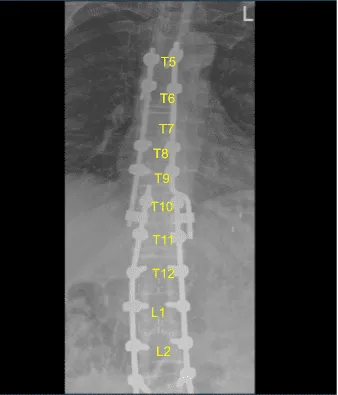

A new cobalt-chrome 5.5 mm Z-rod was selected, cut to proper size, connected to a domino side connector that was already in place across the tulips of the pedicle screws and secured with locking caps after some sort of bending was performed. All locking caps were final tightened with a torque and anti torque devices.

AP and lateral x-rays and final CT scan showed appropriate positioning of all the hardware. Morselized allograft with bone morphogenic protein was packed in lateral gutters on the left side for new fusion arthrodesis. Vancomycin powder was applied. Hemostasis was confirmed. A medium size Hemovac drain was tunneled in a subfascial manner and secured to the skin with a nylon suture.

Sagittal View of Thoracic spine postoperative X-ray

Axial view Thoracic spine postoperative X-ray